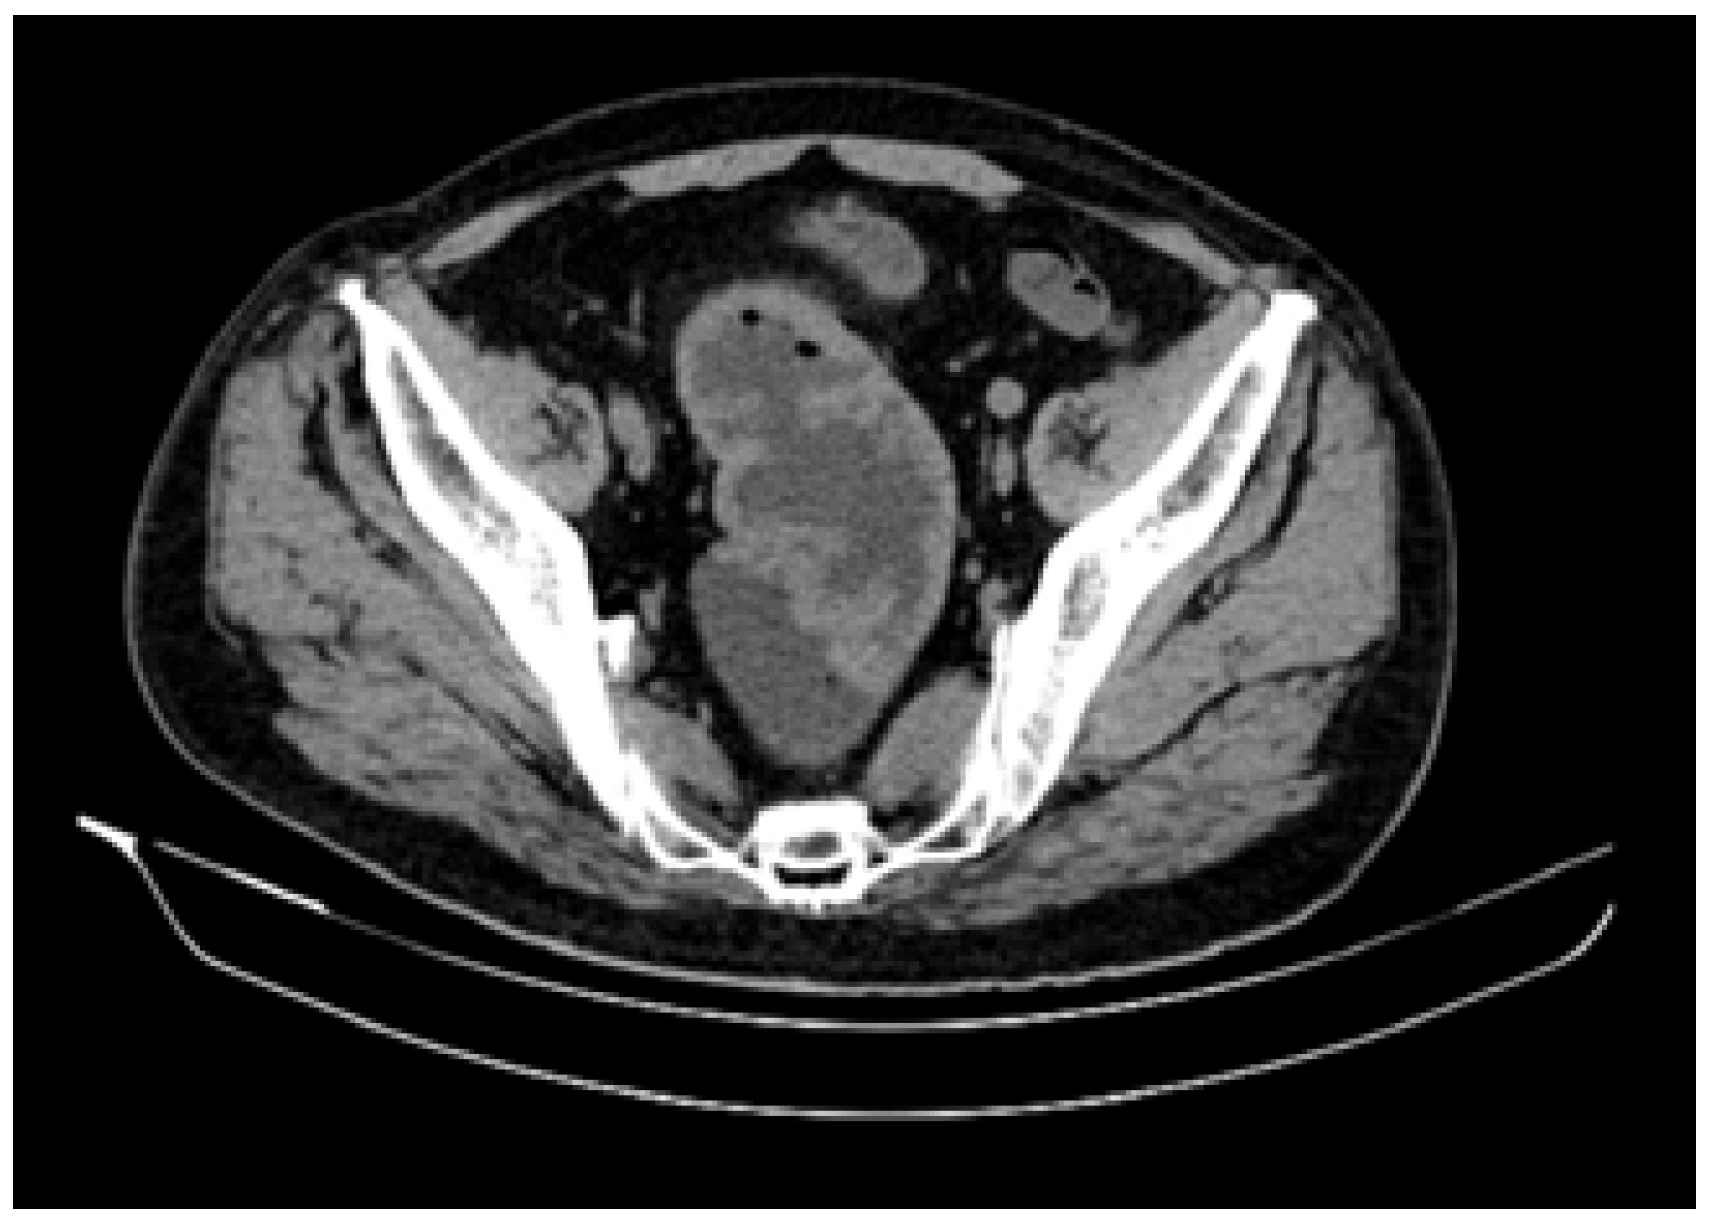

2. Case Presentation